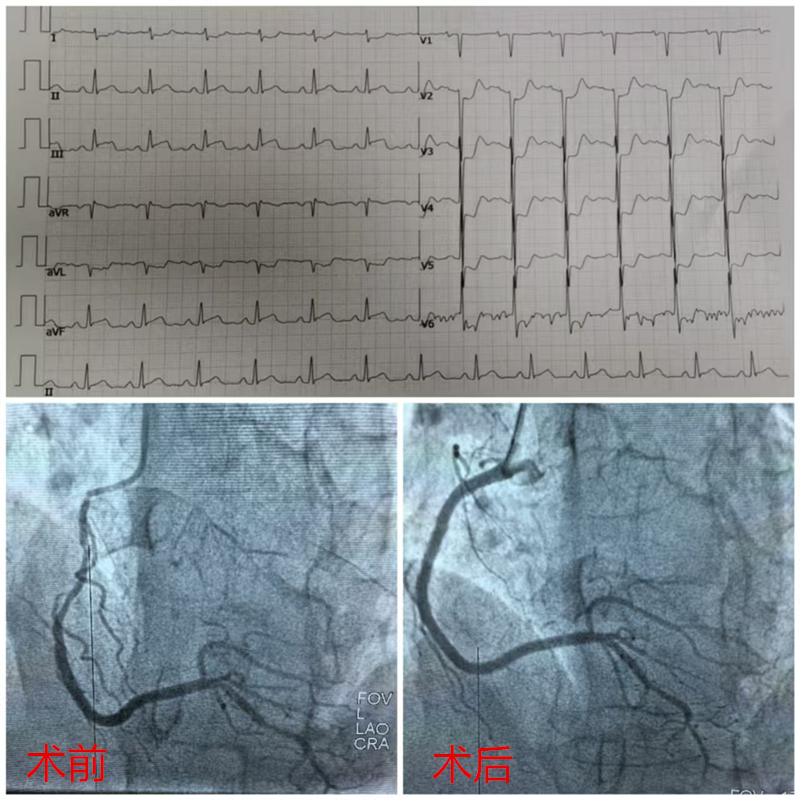

12月24日上午09时许这个阿伯胸痛再发,便来到友谊社区卫生服务中心进行体检,在给其做心电图检查后,结果提示急性下壁心肌梗死。心电图室很快给临床医师报告了危急值,随后当班医师接到危急值后将患者快速转运到友谊社区卫生服务中心抢救室,展开紧急抢救,同时通知医联体单位广西科技大学第一附属医院急诊科120紧急转运。

广西科大一附院急诊科医护人员到达现场后,复查床旁心电图仍为急性下壁心肌梗死,急诊科医师反复与患者及其家属沟通病情,并与心内科医师、导管室联系后做好术前准备。经患者及其家属同意后,立即120车走绿色通道转运到导管室进行手术。

经过广西科技大学第一附属医院急诊科和心内科医护人员的积极抢救,急诊冠脉造影提示右冠脉开口至中段严重狭窄,予紧急植入支架后血管管腔恢复,患者转危为安。

广西科技大学第一附属医院心内科手术前后图片